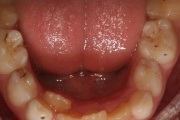

Vali sind huvitav pilt ja me näitame sellega seotud haigust ja sümptomeid